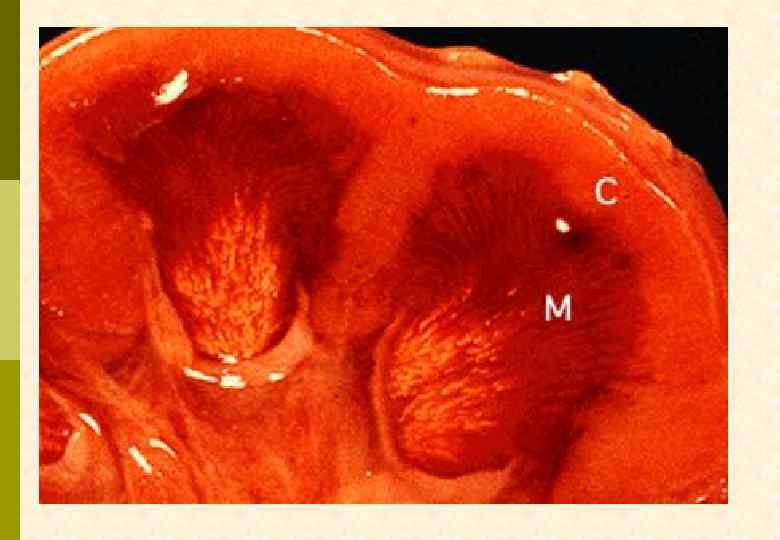

Gonarthritis urica, Historical images. Figure provided by W Grassi and C Cervini. (Published in: O Bollinger, Atlas und Grundriss der Pathologischen Anatomie, Munich: von JF Lehman, 1920. )